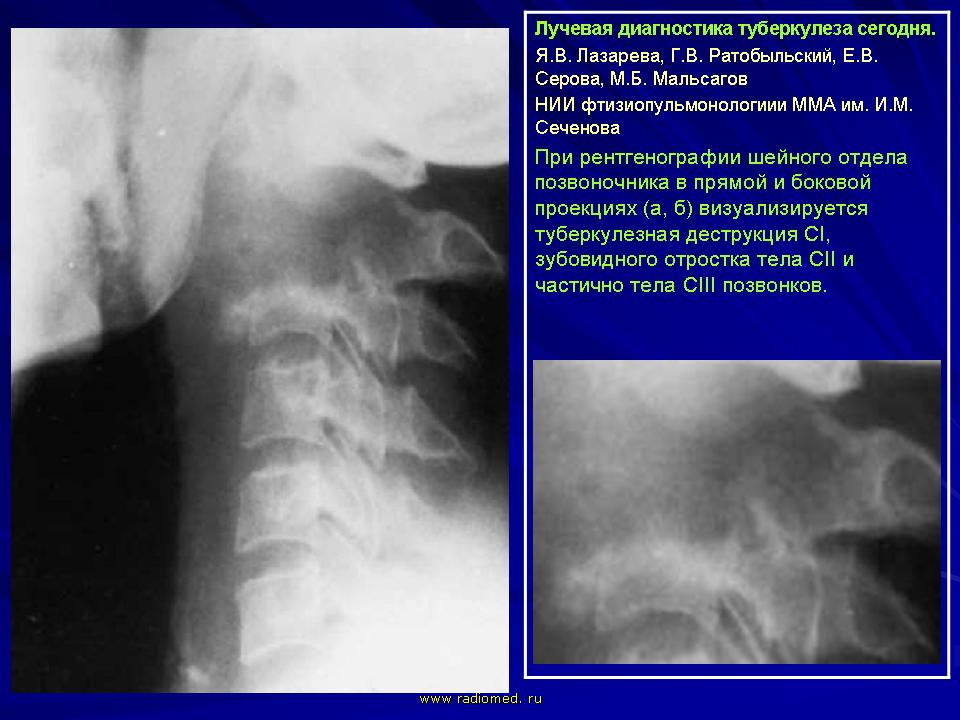

Лучевая диагностика туберкулеза сегодня

Я.В. Лазарева, Г.В. Ратобыльский, Е.В. Серова, М.Б. Мальсагов

НИИ фтизиопульмонологиии ММА им. И.М. Сеченова